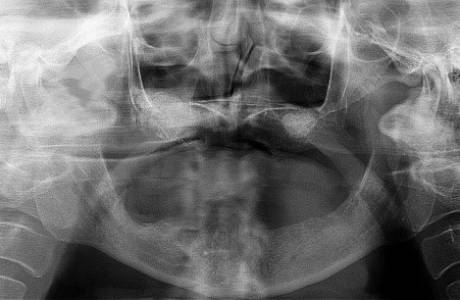

До лечения

Пациентка обратилась с жалобами на травму передних зубов, во время которой были удалены 3 передних зуба.

После лечения

По окончании срока приживления были установлены 4 металлокемарические коронки, которые идеально восстановили эстетику улыбки и вернули пациентке возможность улыбаться.